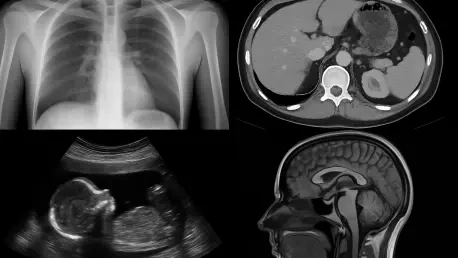

Imagine a future where medical professionals can peer inside the human body with astonishing precision, using a device that not only enhances diagnostic accuracy but also prioritizes patient safety and affordability. A remarkable breakthrough unveiled on September 22, 2025, has brought this vision closer to reality with the introduction of a “crystal” camera. This innovative technology harnesses the power of perovskite crystals, originally developed for solar energy applications, to detect gamma rays and produce high-resolution images of internal organs. By offering a safer and more cost-effective alternative to current methods, this advancement holds the potential to transform nuclear medicine, particularly in identifying conditions like tumors and infections. As the healthcare industry seeks more efficient diagnostic tools, this development sparks curiosity about how such a novel approach could reshape the landscape of medical imaging and improve patient outcomes across the globe.

At the core of this crystal camera’s impact is its enhancement of single-photon emission computed tomography (SPECT), a technique that generates detailed 3D images by detecting gamma rays emitted from a radioactive tracer within the body. Current detectors often grapple with issues like poor resolution and delicate construction, which can hinder their ability to provide clear insights into a patient’s condition. The perovskite-based system, however, excels by distinguishing between gamma rays of varying energies, resulting in sharper and more precise imagery. This improvement is vital for identifying subtle physiological changes that may indicate early stages of diseases such as cancer or neurological disorders, thereby enabling timely interventions that could save lives.

The implications of this enhanced imaging capability extend to the way medical professionals approach diagnostics on a broader scale. With clearer images, specialists can make more informed decisions, reducing the likelihood of misdiagnosis and unnecessary procedures. The technology also supports a more tailored approach to treatment by providing detailed visual data that can guide personalized care plans. For conditions where early detection is critical, such as certain types of infections or degenerative diseases, this level of precision offers a significant advantage. As hospitals and clinics begin to explore the integration of this tool, the potential for improved patient outcomes becomes increasingly evident, highlighting a pivotal shift in how internal health challenges are visualized and addressed.